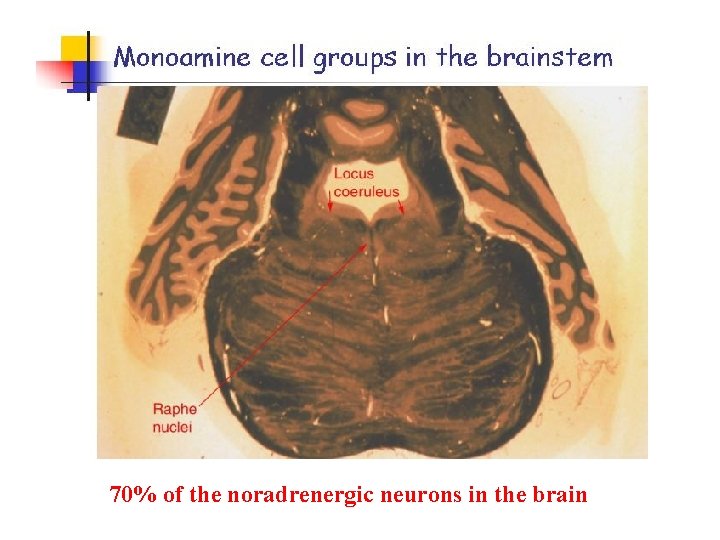

70% of the noradrenergic neurons in the brain